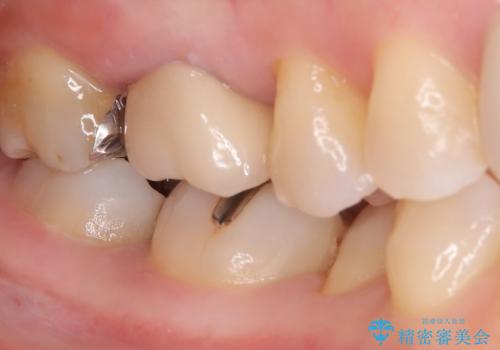

- 主訴:口を開けると所々入っている銀の詰め物が目立つので白い物にやり替えたい。

下顎大臼歯部に入っている保険適用のメタルインレーを、適合性と審美性の良いセラミックインレーでのやり替えとなりました。

セラミックインレーセット時はラバーダム防湿を行っています。